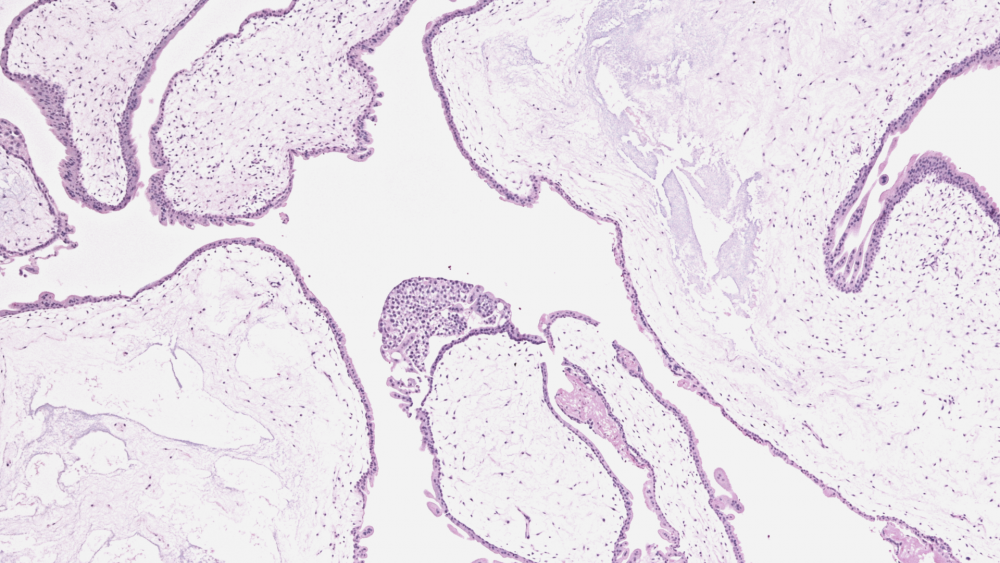

Трофобластические опухоли

Трофобластические опухоли — это опухоли, появление которых всегда связано с беременностью. Они образуются из трофобластов — клеток, которые образуют внешний слой эмбриона и участвуют в его прикреплении к стенке матке, а также в образовании плаценты.